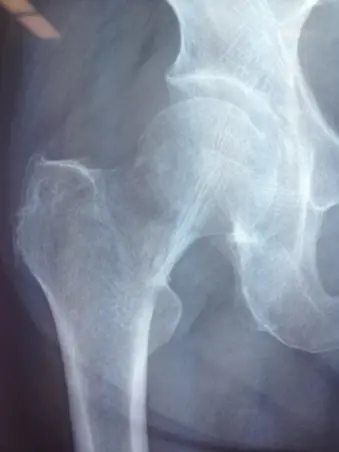

著しい疼痛があるもレントゲンで異常を認めない場合は、骨挫傷や不全骨折(亀裂骨折、若木骨折、竹節骨折)、疲労骨折などの不顕性骨折を認めることがある。不顕性骨折は骨梁の連続性は絶たれているが、骨膜の連続性は保たれているため、レントゲンやCTで異常所見を認めないことが多く,MRI T1強調像で低輝度を呈することによって診断される。外傷後や高齢者でレントゲン上明らかな骨折がないにも関わらず疼痛が持続する場合には、不顕性骨折を疑い、数日後、受傷1週間後のレントゲン再検査や、適宜CTやMRIを施行することが必要である。不全骨折はCTで骨折が判明することもあるが、骨挫傷に関してはCTで有意な所見を認めないことが多く、MRIが最も有用である。また、レントゲンでは骨梁の修復反応により、継時的に骨硬化像を認めるようになる。 全症例にMRIを施行することは困難なことがあり、高齢者の転倒を診る時にはレントゲンでは検出されない骨折があることを念頭に置き、患者にもその旨を説明の上、適宜、レントゲン再検査することが重要である。

左大腿骨頸部骨挫傷の他症例